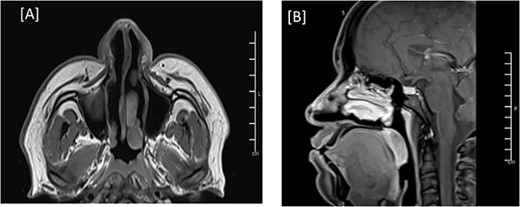

The patient was discharged three days after the surgery with a clean, dry wound and no signs of infection or hematoma collection. The flap was viable with good color and normal capillary refill time. After discharge, the patient had regular follow-ups to assess the wound status and the flap viability. The patient expressed happiness with the shape of his nose. Three months post-op, a follow-up MRI showed total resection of the nasal lesion with no evidence of residuum or recurrence (Fig. 4). The patient was followed in our clinic for 14 months with no signs of recurrence (Fig. 5). During his last visit, he expressed his happiness regarding the relief of symptoms and the shape of his nose.

MRI of the head, and paranasal sinuses (post-op). (A, B) Axial and Mid-sagittal T1 sequence showing total resection of the external nasal mass lesion with a heterogenous enhancement seen likely postoperative changes. No obvious residual mass lesions can be seen.